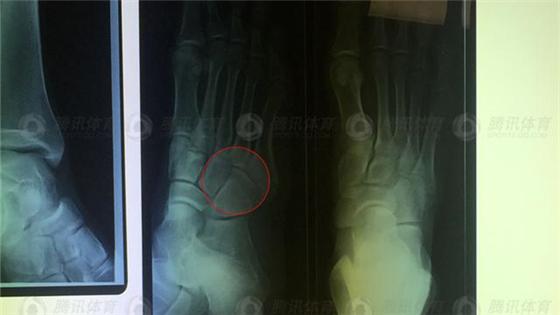

29日上午,正在澳大利亚黄金海岸训练的孙杨在训练时发生意外,右脚第五跖骨骨折,保守估计要6周才能痊愈,自爆“差点疼哭了”的孙杨在接受记者独家电话采访时坚强地说:“这只是训练备战中的小插曲,请大家放心,我一定会顶住!”

然而经过队医的冰敷,孙杨的脚面和踝关节还是肿胀起来,脚面充血,他只能在体能师和教练的搀扶下,单腿蹦着离开力量房。前往医院拍X光片后,诊断为“右脚第五跖骨骨折”。

孙杨右脚第五跖骨骨折,保守估计要6周才能痊愈。